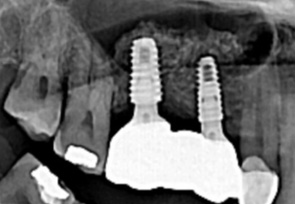

CT촬영 및 영상촬영을 통한 정밀 진단

현재 치아의 상태를 정확하게 검진하는 것이 매우 중요합니다. 치아가 소실 된 시간이 오래될 수록 잇몸 뼈의 소실량이 많아지기 때문에 임플란트를 식립할 수 있는 잇몸뼈의 양과 질을 철저하게 분석하는 것이 매우 중요합니다.

미국치과 임플란트 학회(AAID)의 인정의(AF. Associate.Fellow)인 일등플란트치과의 한순일 대표원장이 다 년간의 많은 임상경험 노하우를 바탕으로 구강 상태에 따른 적합한 뼈이식을 통해 임플란트에 적합한 뼈의 두께를 확보한 후 식립을 합니다.